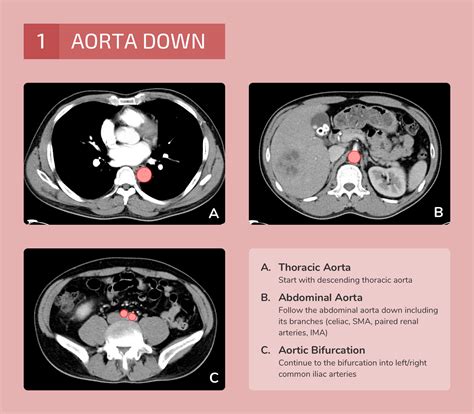

Interpreting the Results of an Abdomen and Pelvis CT Scan

After the scan, a radiologist will review the images and prepare a report detailing any findings. The results of an abdomen and pelvis CT scan can provide valuable information about the presence and extent of various conditions. Some key points to consider include:

• Evaluation of Blood Vessels: The scan can detect blockages, aneurysms, and other issues with blood vessels in the abdomen and pelvis.